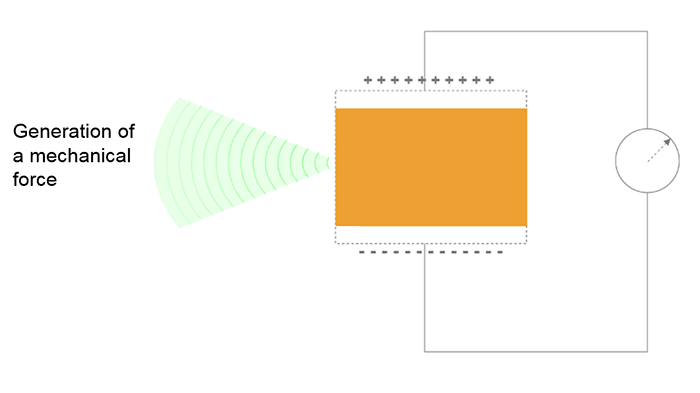

What is the difference between reverse and direct effect? And how do Piezoelectric Elements Generate Ultrasound?

The reverse effect is defined as the generation of a mechanical wave resulting from the application of an electric field. When an electric field is applied, the charge carriers are shifted in the piezoelectric materials, leading to a macroscopic change in the length of the material (inverse piezoelectric effect), thus to the emission of the ultrasound wave. The resulting sound waves propagate in the surrounding medium, where their speed varies according to the density and the elastic properties of the medium.